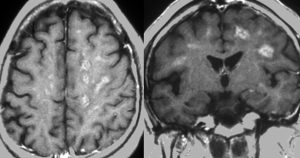

MRI検査で,はっきりわかります。MRI造影剤を入れると均一または斑らに増強(真っ白になる)されて(左側),周囲には脳の腫れ(脳浮腫)がみられます(右側)。できやすい場所は側脳室の周囲・大脳脳基底核・小脳・脳幹部など脳の深いところ(深部白質)です。脳の中に2個以上のリンパ腫が同時にできる多発例というのもしばしばあります